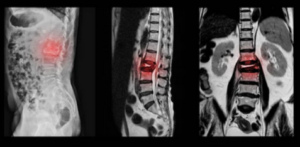

Les tassements vertébraux constituent une pathologie fréquente chez la personne âgée. Ils correspondent à des fractures des corps vertébraux, souvent d'origine ostéoporotique (fragilité osseuse par déminéralisation) et parfois secondaire à une lésion osseuse.

L'indication principale est la fracture vertébrale récente (aussi appelée tassement) le plus souvent d'origine ostéoporotique.

2. Sous contrôle radiologique permanent, les canules sont introduites dans la vertèbre.

3. Une fois en place, le ciment est injecté à l'état liquide jusqu'à obtenir un remplissage satisfaisant de la vertèbre.